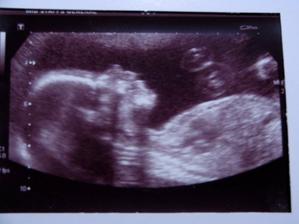

2 Novembra sme boli na ultrazvuk a to nadherne stvorenie co nosim pod srdieckom bude chlapcek....